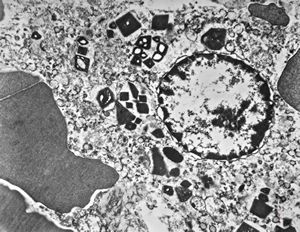

M,62y. | bone marrow - plasmocytoma

M,64y. | bone marrow - plasmocytoma